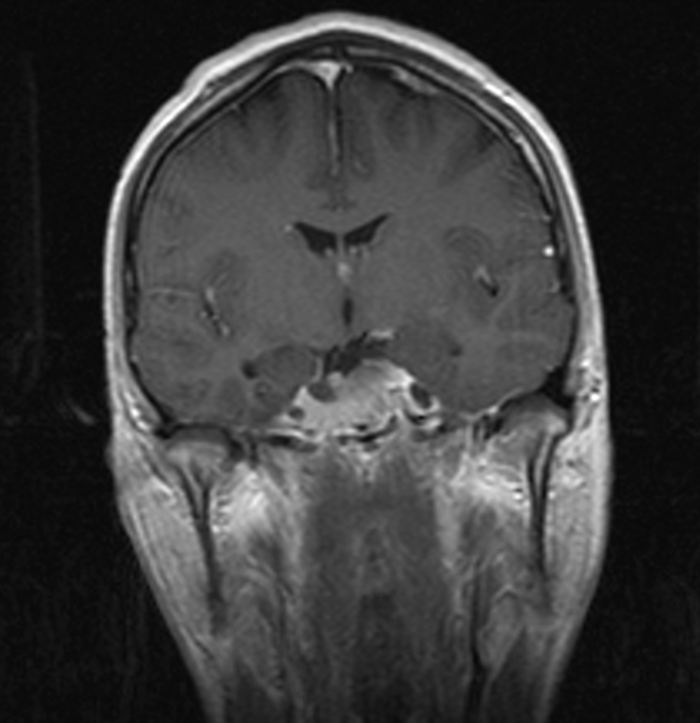

Где то за 3 дня до МРТ заметил, что течь с носа стало значительно меньше. Само МРТ:

Итого опухоль уменьшилась примерно в 2.5 раза от предыдущего размера. Было 64х55х49, потом 52х52х19, а теперь 43х22х18. МРТ почему то делали без контраста, хоть и было в направлении указано, что нужен контраст. Ну и диск не дали.